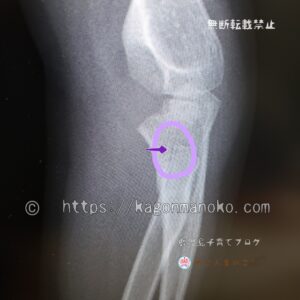

その時のレントゲン写真を許可をいただき特別に写メをしたので載せますネ。

骨の繊維を見ると、黒い陰が1本薄っすら入っているのが分かります。主治医の説明で「この線がヒビである」ことに気づかされます。

レントゲンは違う角度から2枚撮りました。2枚目が次の写真です。この角度でも骨に黒い筋が1本入っているのが分かります。